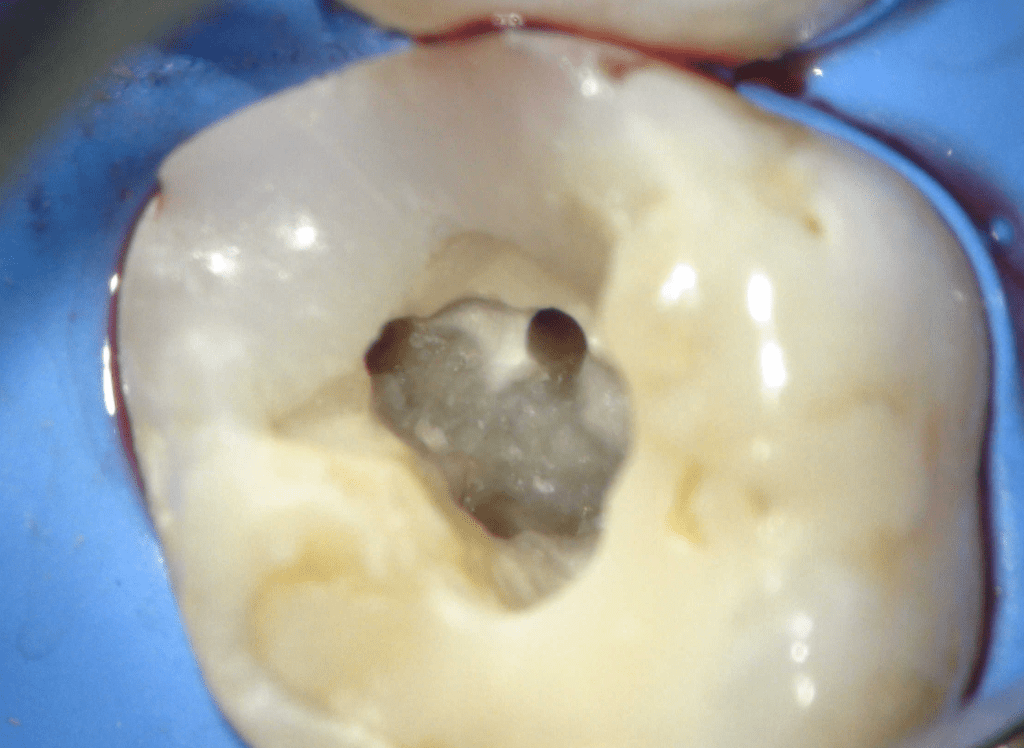

Fisura, remoción amalgama para explorar